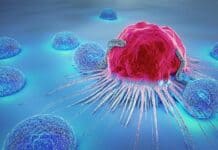

ক্যানসার চিকিৎসার অভিনব পদ্ধতি প্রিসিশন অনকোলজি

জীবন্ত প্রাণীর কোষে ডিএনএ বা ডি-অক্সিরাইবো নিউক্লিক অ্যাসিড থাকে। এ জিনোমিক উপাদান কোষ বৃদ্ধি, বিকাশ, গঠন, রক্ষণাবেক্ষণ এবং রোগ-বালাইসহ প্রয়োজনীয় তথ্য ধারণ ও নিয়ন্ত্রণে...

জরায়ুতে টিউমার মানেই কি ক্যানসার?

দেশের অনেক নারী জরায়ুর টিউমার সমস্যায় ভুগছেন। এতে করে তারা ক্যানসার আতঙ্কে আছেন।

তবে বিষেশজ্ঞ চিকিৎসকরা বলছেন, জরায়ুতে টিউমার মানে ক্যানসার নয়। টিউমার হলেই তা...